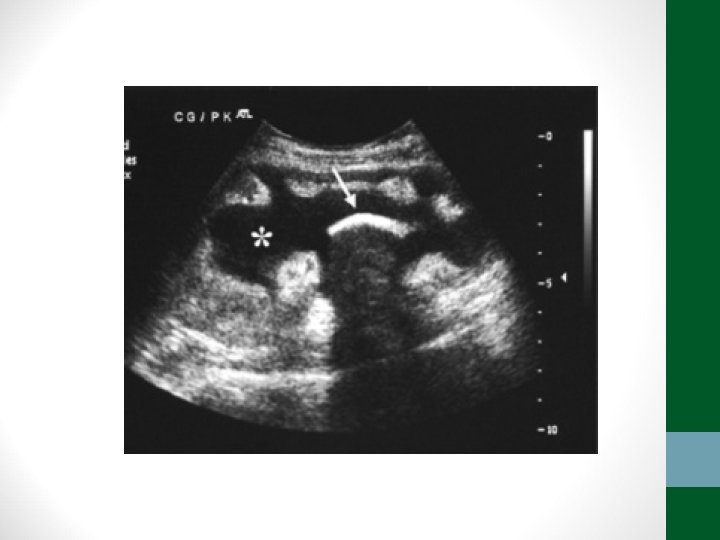

Exames de Imagem • Abdome Agudo Hemorrágico: • Radiografia simples de abdome: decúbito, ortostase e cúpulas diafragmáticas (apenas para descartar outras causas) • USG Abdome é o exame mais importante, pode ser necessária USG transvaginal • TC de Abdome em casos selecionados

Colecistite Alitiásica • Pacientes politraumatizados, PO de grandes cirurgias, internados em UTI • Fatores de risco: choque, IRA, uso de NPT, febre, jejum prolongado, restrição hídrica, desidratação, uso de opiáceos • Fisiopatologia: aumento da viscosidade da bile e hipoperfusão da veícula biliar – estase funcional • Diagnóstico difícil – leucocitose, febre, distensão abdominal • Confirmação com USG abdome – a beira do leito